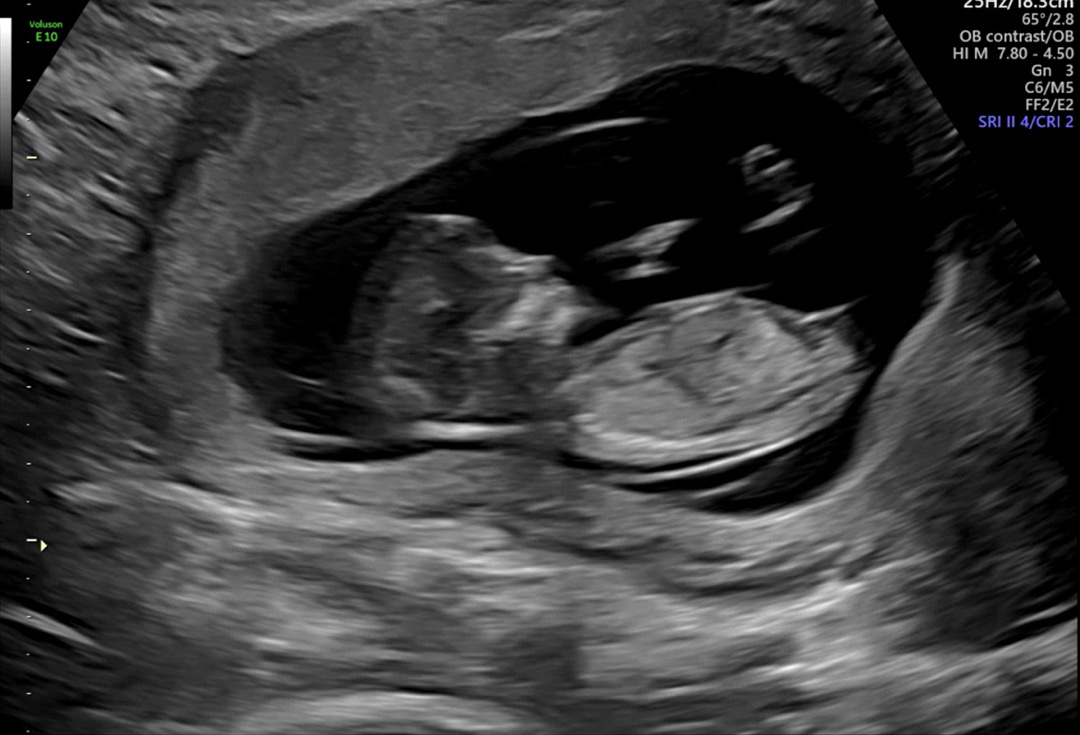

딸일까요 아들일까용..?? 🍑??🌶️??